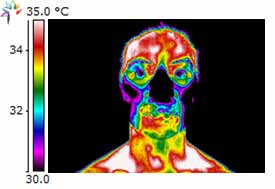

Dental Case Study 1

June 2010 Initial thermography performed.

(L)TMLAT = 0.5 ºC and Hyperthermia in the region of 1st – 2nd premolar.

Dental Exam – no abnormalities, Bite Splint was done. Patient refused any additional dental work.

February 2011 patient complained of sensitivity on chewing in the lower right side.

Exam showed gingival inflammation and furcation involvement of 7mm pocket. Extraction was performed.